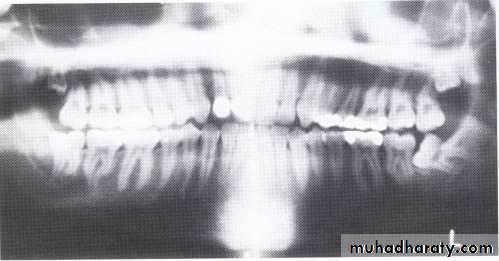

Developmental absence of all maxillary premolars and both mandibular second premolars. Note the retention of the maxillary primary canine as a result of the posterior position of the maxillary permanent canine.